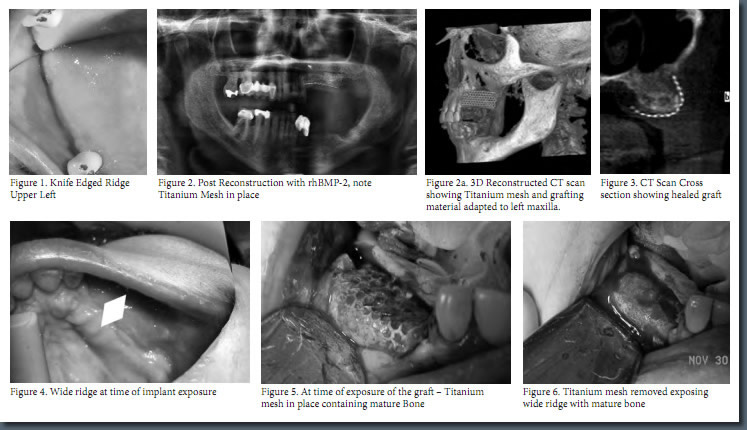

Mark Stein, D.D.S., M.D. of New York Oral and Maxillofacial Surgery Dental Implant Center was recently published in New York County Dental Society's 18th volume of Dentists’ Quarterly for his article on the newest technology available to help bone grafting and dental implants, the recombinant human bone morphogenetic protein in New York City. Dr. Stein’s article, “A New Approach to Reconstructing Difficult Maxillary Defect— Recombinant Human Bone Morphogenic Protein,” depicts an easier, less invasive, safer, and more efficient method of gaining enough bone support to anchor dental implants. Bone Morphogenic Protein (BMP) in NYC actually stimulates bone formation at the site in need of more bone support, circumventing the need for bone grafts in order to insert dental implants.

According to Mark Stein, D.D.S., M.D., dental professionals are leaning away from removable dentures and towards permanent dental implants as the first method of choice in order to repair missing teeth. Some patients, however, lack the necessary bone density to make dental implants a viable option. Until recently, bone grafting in NY was the standard procedure to improve a person’s bone density and prepare their jaw for dental implants in NY. Bone grafting, however, involves harvesting bone from a donor location, such as another location on the mouth or the hip, and transferring the harvested bone to the jaw. After bone grafting, patients must wait 4 to 9 months for the grafting site to heal before they may receive implants. This process was necessary to enhance bone density and was the only means to achieve more bone tissue in the needed area. With the advent of bone morphogenic protein in NY, oral surgeons, such as Mark Stein, D.D.S., M.D., can achieve more bone in the needed area by stimulating the bone itself to produce more bone cells.

Recombinant human bone morphogenetic protein Bone Graft in New York City is comprised of two active ingredients: a manmade protein found naturally in the body and an absorbable collagen sponge (ACS). The protein stimulates the formation of new bone, and the absorbable collagen sponge regulates when the protein is released over a period of time. The absorbable collagen sponge also acts as a trellis on which the newly stimulated bone may form, grow, and take shape. Eventually, the body absorbs the ACS with actual bone. Using bone morphogenic protein in NY instead of traditional bone grafting in New York to increase bone density completely eliminates the need for donor bone from a donor site. This method provides patients with an easier, less invasive procedure to ready the mouth for dental implants in New York.

Do view Dr. Stein’s complete article, click on the following title: A New Approach to Reconstructing Difficult Maxillary Defect— Recombinant Human Bone Morphogenic Protein.